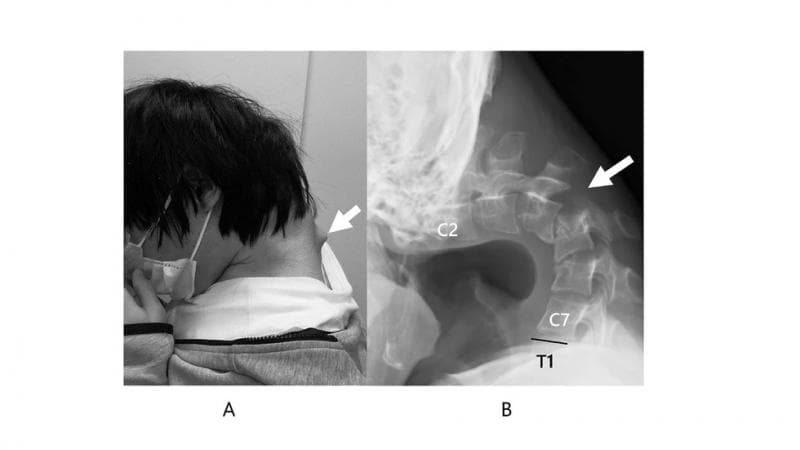

Jadi, ceritanya sebelum akhirnya didiagnosis mengalami sindrom kepala menunduk, laki-laki ini mengalami nyeri leher yang cukup parah hingga sekitar setengah tahun. Lambat laun, dia semakin kesulitan mengangkat kepalanya, serta sulit menelan makanan atau minuman, yang akhirnya berimbas pada penurunan berat badannya secara drastis.

Setelah diperiksakan ke dokter, terlihat adanya benjolan belakang pada bagian tengkuk lehernya. Ternyata, tulang belakangnya sudah bergeser jauh dari posisi normalnya dan adanya jaringan otot yang nggak wajar akibat terus berada dalam postur tubuh yang nggak wajar selama bertahun-tahun.